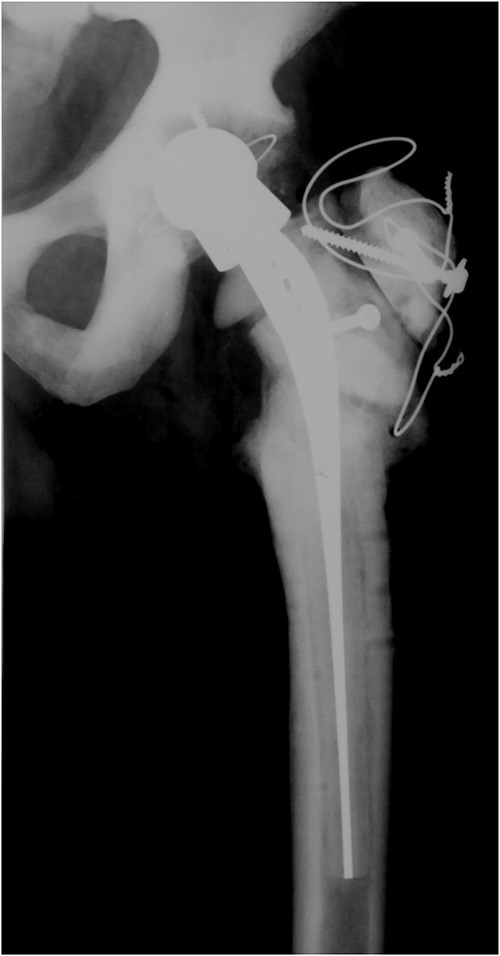

In 2008, the patient complained about increasing pain in the left hip. Laboratory tests were normal and X-ray imaging showed a loose cup which was replaced with a reinforcement ring and a cemented cup and the loose femoral component which was exchanged with a cementless revision stem (Fig. 2). Routine intraoperative tissue samples were positive and Staphylococcus epidermidis was isolated. A 3-month antibiotic treatment consisted of ciprofloxacin and rifampicin successfully cured the infection.

Anteroposterior radiograph of the left hip after revision surgery in 2008.